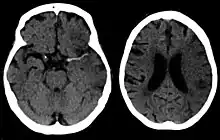

A CT showing early signs of a middle cerebral artery stroke with loss of definition of the gyri and grey white boundary

Dens media sign in a patient with middle cerebral artery infarction shown on the left. Right image after 7 hours.

Stroke is diagnosed through several techniques: a neurological examination (such as the NIHSS), CT scans (most often without contrast enhancements) or MRI scans, Doppler ultrasound, and arteriography. The diagnosis of stroke itself is clinical, with assistance from the imaging techniques. Imaging techniques also assist in determining the subtypes and cause of stroke. There is yet no commonly used blood test for the stroke diagnosis itself, though blood tests may be of help in finding out the likely cause of stroke.[63]